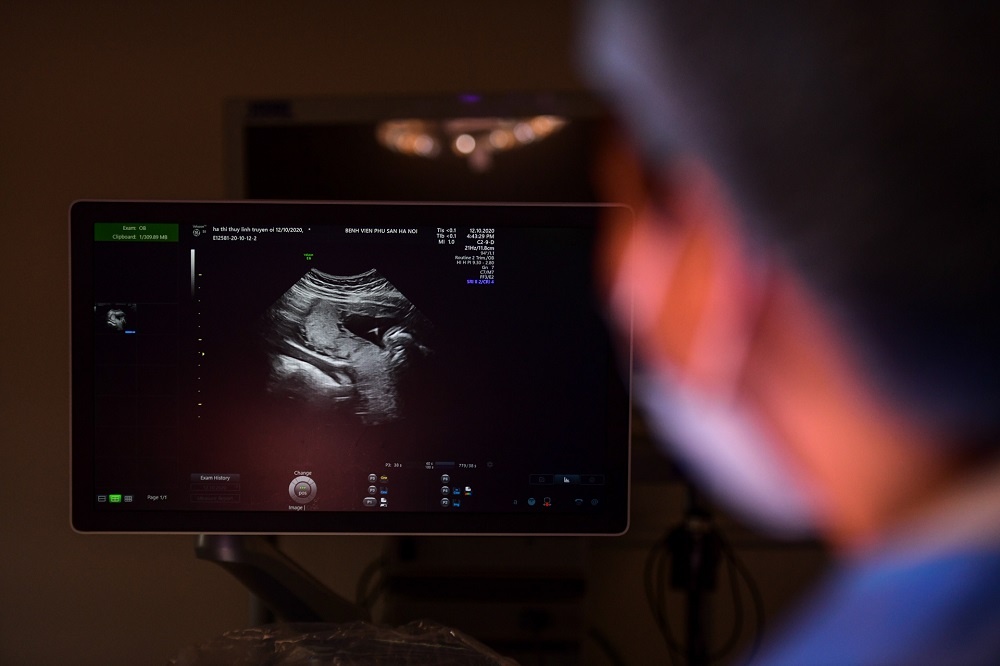

PGS Trần Danh Cường cho biết nhiều người bị ám ảnh bởi những quan niệm về giới tính khi luôn xin bác sĩ tiết lộ giới tính của thai. Ảnh: Quỳnh Trang.